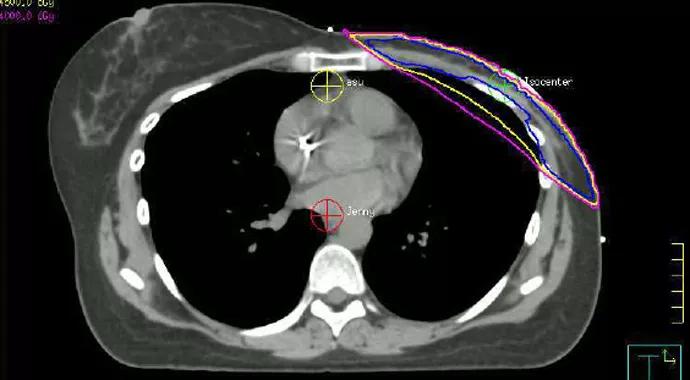

Three-Dimensional Radiation Planning

CT scans for radiation planning ensure that radiation beams are aimed directly at the affected breast tissue. “You can see how much of the heart is being included in the [radiation beam] field,” Dr. Tendulkar says. Today, the shape and size of the radiation field is designed to minimize exposure to the heart. Through conformal treatment planning, portions of the heart are blocked out of the treatment path.